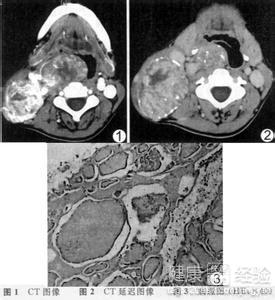

1這裡,我們先講一下什麼是先天性甲狀腺異位,異位甲狀腺是一種胚胎發育畸形,多見於1-10歲的幼兒,甲狀腺不在頸部正常位置而出現在甲狀腺下降途中的其他部位,其中以胸骨後甲狀腺腫及甲狀腺舌管囊較為常見。

2新生兒先天性甲狀腺異位的患者其臨床表現為:胸骨後甲狀腺腫因胸骨後縱隔間隙甚窄,可引起較明顯的壓迫症狀。出現咳嗽、呼吸困難等症狀,引起聲音嘶啞等;胸骨或脊柱受壓可出現胸內悶脹感或胸背疼痛。